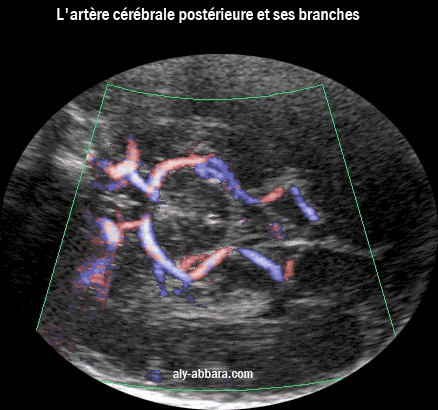

Coupe axiale (coronale) du cerveau fœtal à 35 SA

Le polygone de Willis et l'artère cérébrale postérieure sa interne principale branche,

l'artère calcarine

L'artère cérébrale postérieure et sa branche interne pricipale, l'artère calcarine